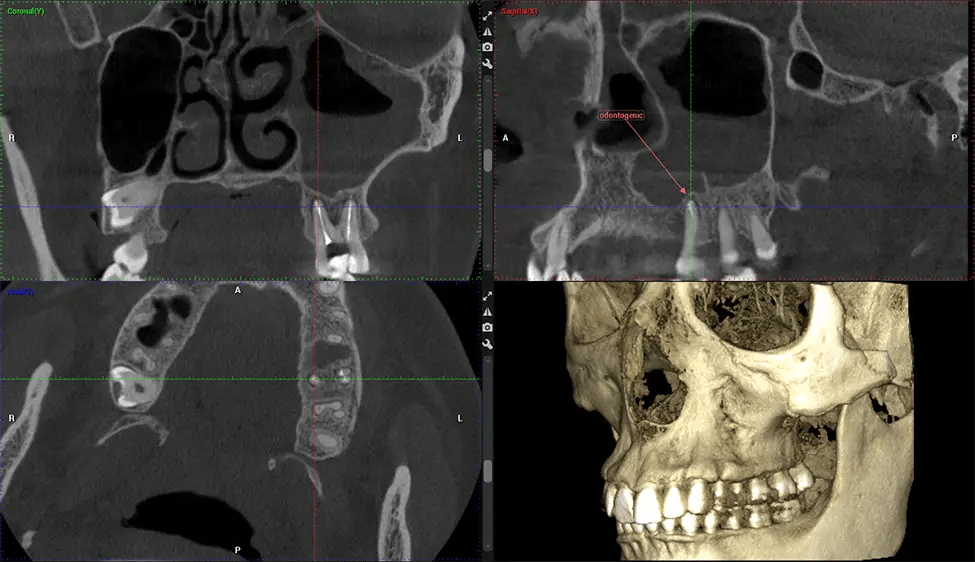

This 3D scan, called cone beam computed tomography, gives your dentist a more complete image of your oral anatomy and disease processes than a traditional X-ray. Unlike conventional X-rays, which capture a 2D image of your mouth from various angles, a 3D scan takes multiple digital X-rays for one image. It provides a complete view of your jaw, teeth, nerves, and soft tissues. This enhanced view allows dentists to detect minor issues not visible in traditional 2D scans, such as impacted wisdom teeth or bone fractures in the sinus cavity.

There are many benefits to using CBCT technology, especially compared to the traditional 2D X-ray format. One of the most significant advantages of CBCT scans is that they provide much more information than traditional X-rays. A scan lets your dentist see images from all angles of your jaw and mouth, including your sinuses, nasal cavity, cheekbones, and other surrounding areas. This added information helps your dentist craft a comprehensive treatment plan that addresses all aspects of your oral health.

Oral and Maxillofacial Surgeon Complex oral surgeries, orthognathic (jaw) surgery, and removal of impacted teeth. Offers precise, three-dimensional visualization of the skull, jaw, and craniocervical junction to enhance diagnostic accuracy and minimize surgical risks.

ENT Physician Diagnosing obstructive sleep apnea (OSA) and evaluating sinus and nasal cavity anatomy. Visualizes the entire pharyngeal airway to measure volume, pinpoint constrictions, and plan corrective surgery if needed.